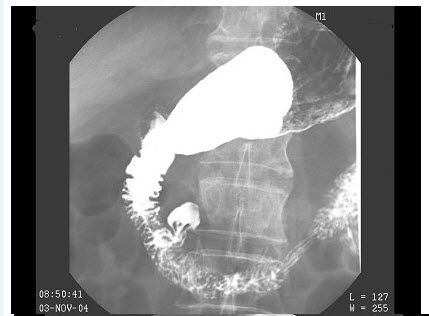

男,80岁,脐周隐痛反复发作半年,加重1月,体检:脐周压痛,以脐上为主,无反跳痛,结合图像,最可能的诊断为()

C、胃癌

D、笔杆征

E、降段憩室

E